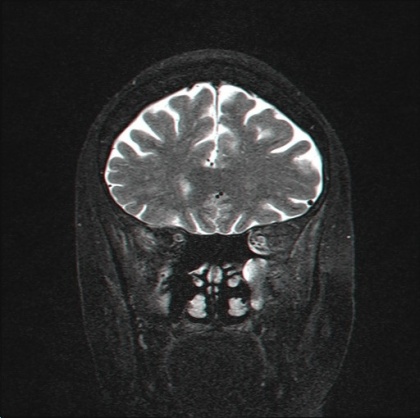

בכל מרכז המתמחה בטיפול במנינגיומות מקובל לקיים מעקב רב תחומי, במהלכו מתבצעת הערכה נוירואופתלמולוגית, המאפשרת בדיקה מדוקדקת המפרידה בין קיומה של הפרעה בראייה משנית למנינגיומה, לבין הפרעה מקומית בעין - צורך במשקפיים, ירוד (Cataract), מחלה של הרשתית וכדומה; מעקב נוירוכירורגי ומעקב הדמייתי באמצעות הדמיה בתהודה מגנטית (MRI, Magnetic Resonance Imaging) שנתית, לאיתור סימני התקדמות של הגידול. נהוג שבכל מקרה שבו מתעורר חשד לגדילה של המנינגיומה, או כאשר מופיע נזק חדש או מתקדם בראייה, מתקיים דיון רב תחומי בין הנוירוכירורג, הנוירואופתלמולוג והנוירורדיולוג (Neuroradiologist). בדיון טיפוסי שכזה דנים באפשרויות הטיפול בחולה, תוך שקלול מצבו הרפואי הכולל.